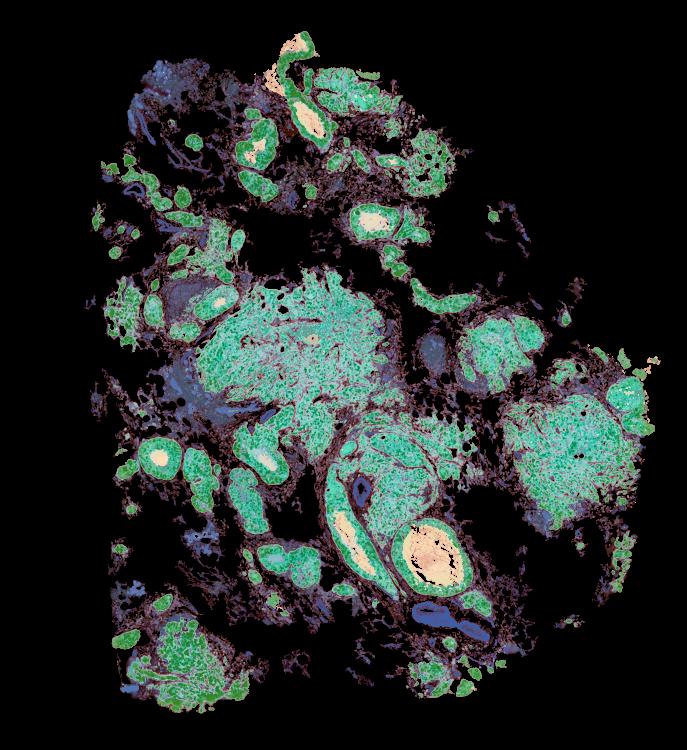

Atlas: Washington University

Breast cancer (BC) is defined by distinct molecular subtypes with different cells of origin. The transcriptional networks that characterize the subtype-specific tumor-normal lineages are not established. In this work, we applied bulk, single-cell and single-nucleus multi-omic techniques as well as spatial transcriptomics and multiplex imaging on 61 samples from 37 patients with BC to show characteristic links in gene expression and chromatin accessibility between BC subtypes and their putative cells of origin. Regulatory network analysis of transcription factors underscored the importance of BHLHE40 in luminal BC and luminal mature cells and KLF5 in basal-like tumors and luminal progenitor cells. Furthermore, we identify key genes defining the basal-like (SOX6 and KCNQ3) and luminal A/B (FAM155A and LRP1B) lineages. Exhausted CTLA4-expressing CD8+ T cells were enriched in basal-like BC, suggesting an altered means of immune dysfunction. These findings demonstrate analysis of paired transcription and chromatin accessibility at the single-cell level is a powerful tool for investigating cancer lineage and highlight transcriptional networks that define basal and luminal BC lineages.